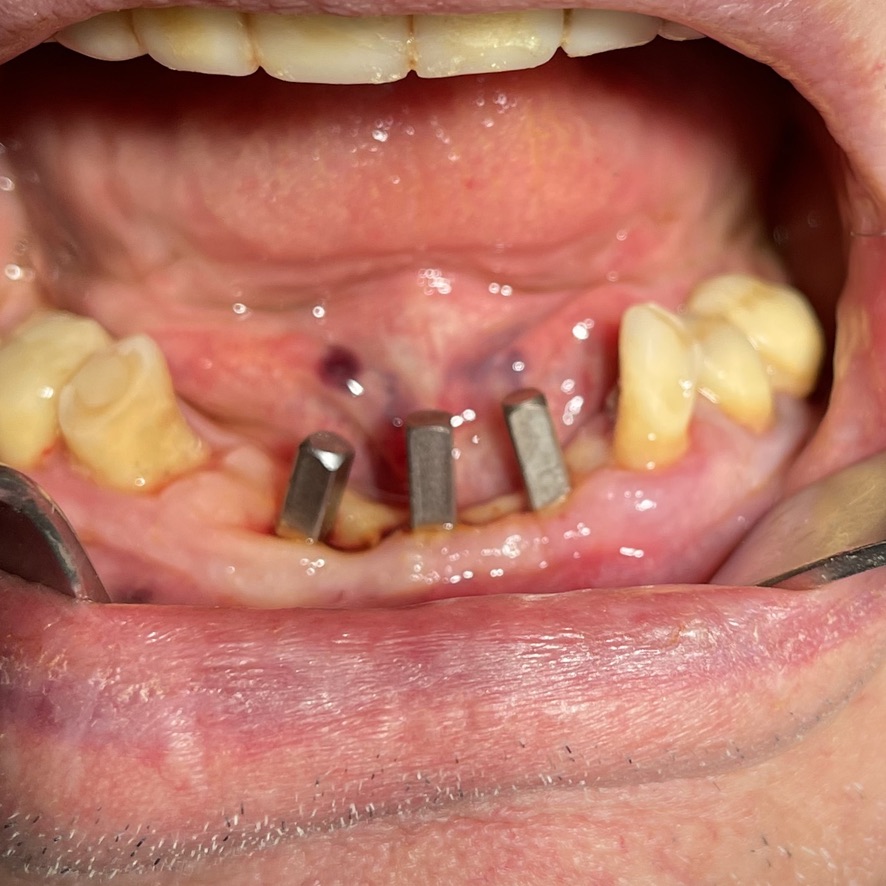

CLINICAL CASE combined with news n.6. Rehabilitation of 04/28/2021

In particular, I consider the following aspects to be significant:

• 8 Presence of two mini-plants in 11-12

• 9 Presence of a welded bar in the upper sector

• 10 Severe periodontal disease of the lower sector

• 12 Implant failure of lower Tramonte implant, implant prior to 2004, in the context of general periodontal disease

• 13 The insertion of the three implants did not involve bone or connective tissue grafts

• 14 It did not make detachments necessary

• 15 It was not necessary to isolate the emergencies of the inferior alveolar nerves

• 16 Since we are dealing with high-density bone, we resorted to the helical drill, an instrument rarely used by us because it is not necessary and because there are areas where its use involves surgical risks that are not acceptable to us. In addition, this drill removes discrete amounts of bone that we prefer to remain where nature has put it. It is interesting that the diameter of the cutter is only 2 mm

• 17 Being dense bone, the implants used had a diameter of only 4 mm after tapping with the corresponding tap

The images provide additional information in the captions.